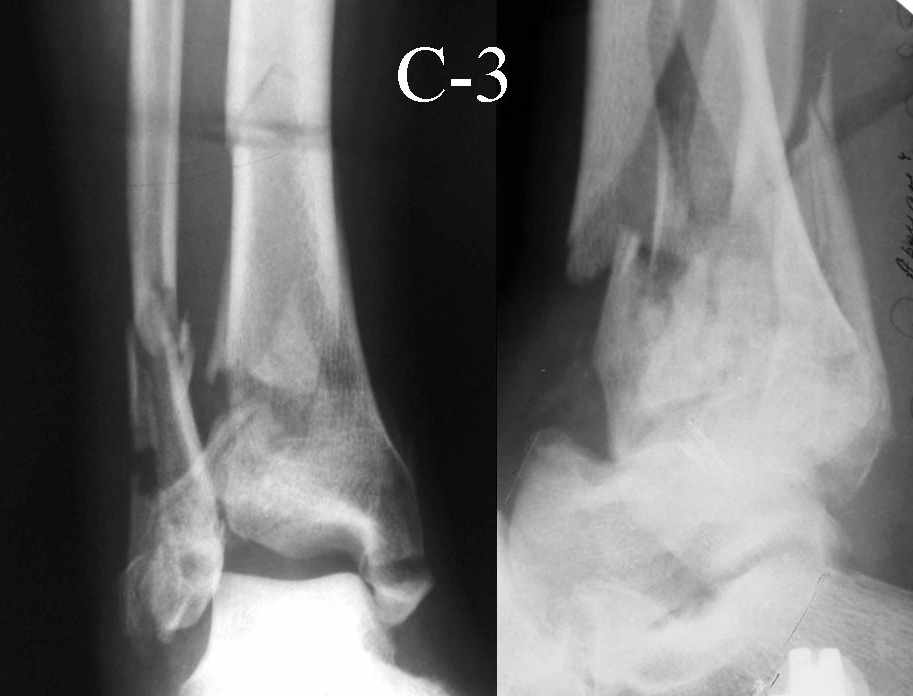

На рентгенограммах типичный перелом пилона по типу С-3. есть опыт до 100 открытых опреаций у нас в клинике. 20 примерно в год. Принцип один -все внутрисуставные переломы нуждаются в открытой репозиции и внутренней стабильной фиксации. При поступлении КТ не надо, так как получается только нагромождение костей. Истинной картины нет. Главное восстановить длину малоберцовой кости - это ключ к успеху. При поступлении меньше всего надо думать о сосудистых расстройствах, т.к. сама операция и репозиция даже сначала частичная даёт улучшение сосудитых нарушений. Причём очень быстро. Операция в 2этапа. При поступлении доступ позади наружной лодыжки, причём обязательно. После этого репозиция малоберцовой кости и фиксация пластиной 1/3 трубки под винт 3,5. Дренаж и любой аппарат наружной фиксации. Затем после спадения отёка на 5-7-10 день аппрат снимается и дугообразный разрез спереди от медиальной лодыжки 10-12 см. Главной чтобы расстояние между 1 и вторым разрезом было не меньше 7-8 см. Тогда не будет некрозов лоскутов. Таранная кость используется как матрица на неё укладываются отломки и фиксируются пицами. Ренг-контроль. Отломки лежат все отдельно, но ничего не высыпется. При переломах С-3 всегда нужна костная пластика (из крыла). Фиксация пластиной лист клевера простой или LCP. Гипс не нужен. Дренаж до 48 часов. Операция длится 3-4 часа обязательно без жгута. Посылаю примерно такой же случай.

Посылаю результат лечения предыдущего больного через год.

С уважением Дрягин